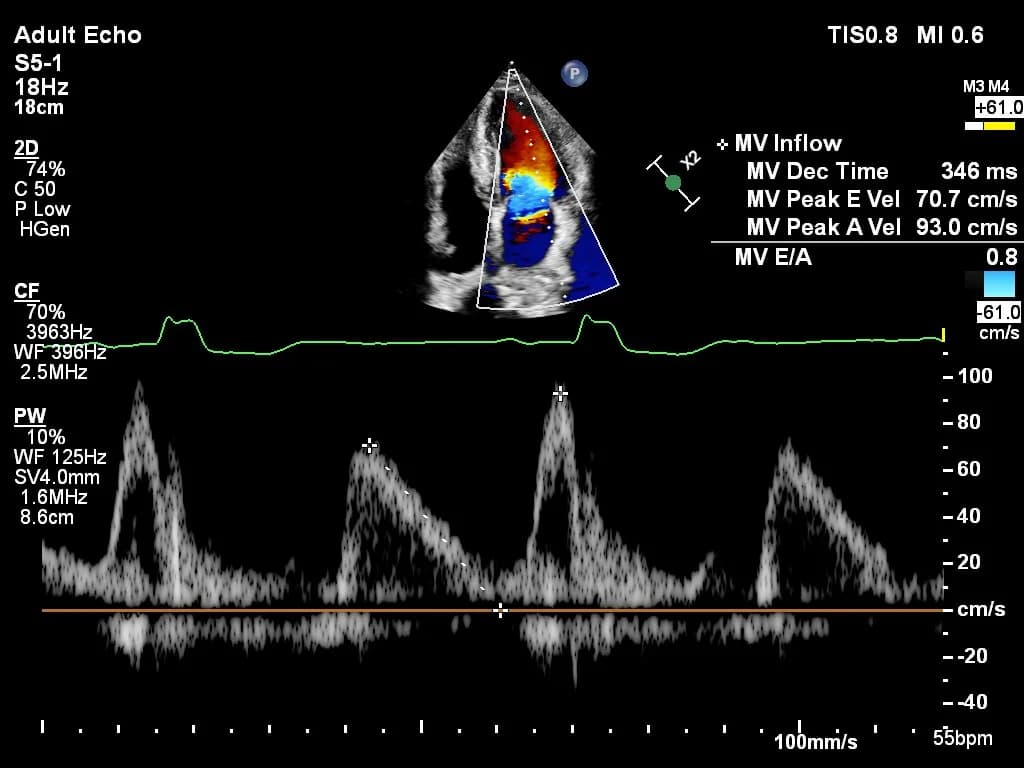

Practice with anonymized echocardiography cases from real clinical encounters.